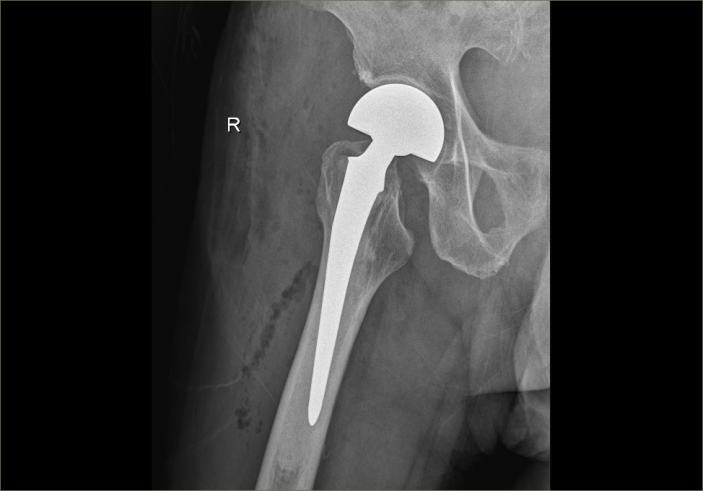

爲了手術能順利開展,骨科主任吳志斌一面邀請我院内科專家會診,對内科疾病進行積極治療,爲手術開展創造有利條件,一面召開術前讨論,精心拟定“右側人工股骨頭置換術”的手術方案,并對術中、術後可能出現的情況制定相應對策。

經過内科對症治療後,患者病情穩定,吳主任帶領團隊抓住時機,在麻醉科的配合下,果斷爲其施術。根據術前拟定方案按部就班實施手術,娴熟地切開組織、修整股骨近端、安裝骨柄假體和雙動股骨頭、複位髋關節,并細心檢查髋部活動度良好、雙下肢等長後,縫合切口順利完成手術。因術前準備充分,整個術程一氣呵成,既縮短手術時間,也減少術中出血,有效降低手術給患者帶來的傷害。